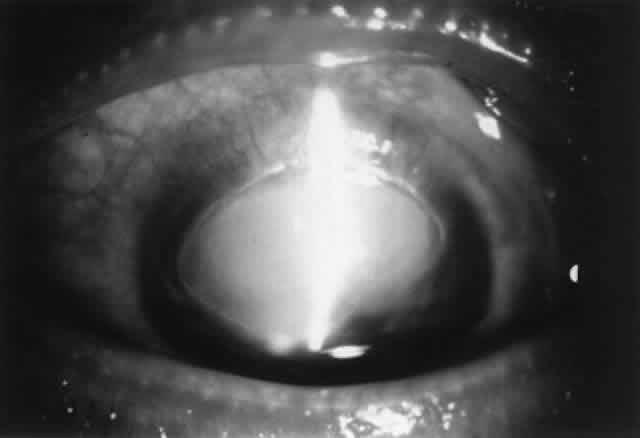

The Role of Crossmatching and Tissue Typing

HLA antigens have been described in all layers of the cornea. Both class I and II antigens are found in the corneal epithelium, most of the class II antigens being found on Langerhans cells, which are located more in the corneal periphery. Class I antigens exist on stromal keratocytes.144–147 Class II antigens have recently been found in the corneal stroma on dendritic cells.145 Although previously not thought to exist on the corneal endothelium, more sensitive methods have identified class I antigens here.146 Class II antigens have not been identified on normal endothelium but have been detected on the endothelium of rejected corneas.148 Corneal endothelial and stromal cells can be induced to express HLA-DR antigens.149 A and B blood group antigens have also been identified in the cornea.150

The presence of lymphocytotoxic antibodies to donor HLA antigens is strongly associated with allograft rejection in transplantation of vascularized organs.151,152 For this reason, crossmatching to screen the recipient serum for lymphocytotoxic antibodies is standard procedure in transplantation of vascularized organs. Lymphocytotoxic antibodies can form after penetrating keratoplasty.153 However, a causal relationship between the formation of such antibodies and subsequent rejection has not been established.149 Thus, the role of preformed lymphocytotoxic antibodies in corneal graft rejection is not clear.

Current thinking has been that the HLA-A, -B, and -DR antigens are the most important factors in immunologic graft rejection. Although a lesser number of older studies do not support the benefit of HLA matching,154–157 numerous studies do show a beneficial effect of HLA matching, including a correlation with the degree of matching.131–134,158–167 However, proper conclusions are clouded by study design problems (e.g., small numbers, lack of controls, retrospective rather than prospective, unsatisfactory follow-up) and statistical methods. Also, studies have not consistently used crossmatch testing to detect the presence of preformed lymphocytotoxic antibodies in the recipient serum.139 Therefore, the role of HLA matching in lessening the risk of corneal graft rejection is unclear.129,139